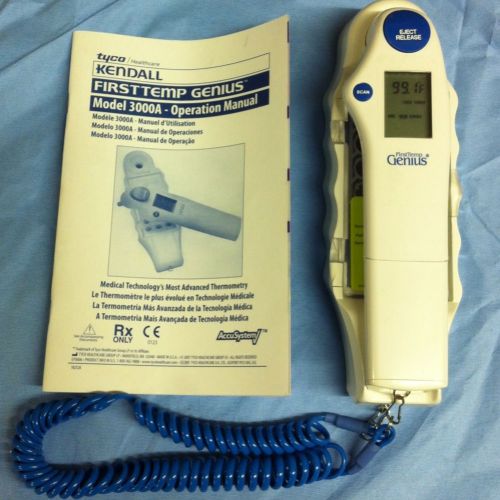

TYCO KENDALL FIRST TEMP GENIUS PROBE COVERS 8884-810055 - 2100PCS

Kendall FirstTemp Genius Infared Tympanic Thermometer Model 3000A Great Cond.